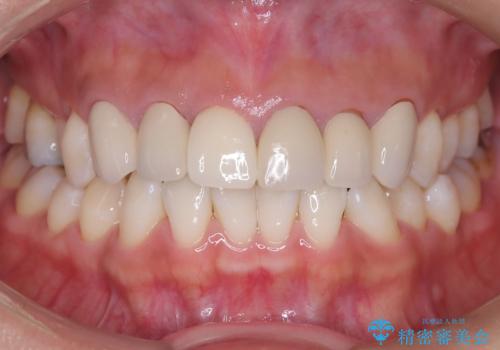

前歯のクラウンをやり変え、歯肉のラインも美しく

担当医 河口智英